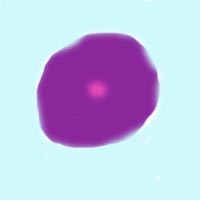

The abnormal endometrium is also under hormonal control and the same changes that occur in the normal endometrium occur in the abnormal endometrium. The next illustrations show a nodule in the different stages of menstruation. This nodule is situated on peritoneum as illustrated in the next drawing.

The next drawing shows a cross section through this module just after a menstration

The purple line represents the endometrial epithelium cells and the blue line the peritoneum. Because the endometrium is in a foreign region and not in contact with the muscle of the uterus (womb), the epithelium curls at the edges. The edges meet and a spherical structure is formed. If endometrium